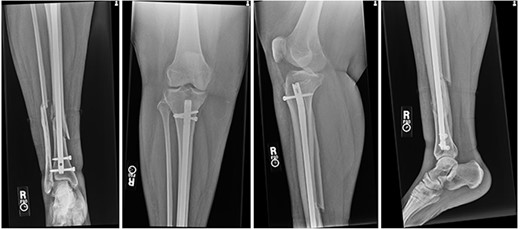

The patient was taken to the operating room on the same day for irrigation and debridement and suprapatellar nailing of the tibia. The cannula and trocar wire were driven in place, and the bone was reamed up to 11.5 mm. A 10 mm diameter Smith and Nephew nail was inserted, and two proximal and two distal interlocking screws were placed. No complications nor injury to the cartilage were noted at the time, and imaging demonstrated appropriate reduction of the fracture (Fig. 2). The patient was discharged home the next day with permission to weight bear as tolerated.

Postoperative radiographs demonstrating reduction of distal tibia/fibula fracture.